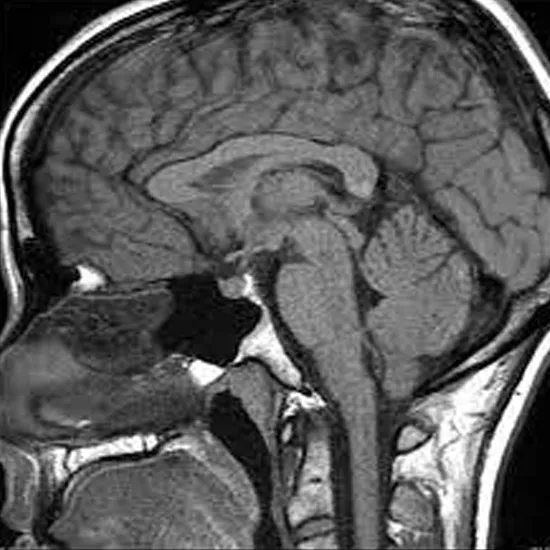

A pituitary MRI is an imaging test that creates images of the pituitary gland (a tiny gland in the brain regulating hormones and other glands in the body) and surrounding brain regions.